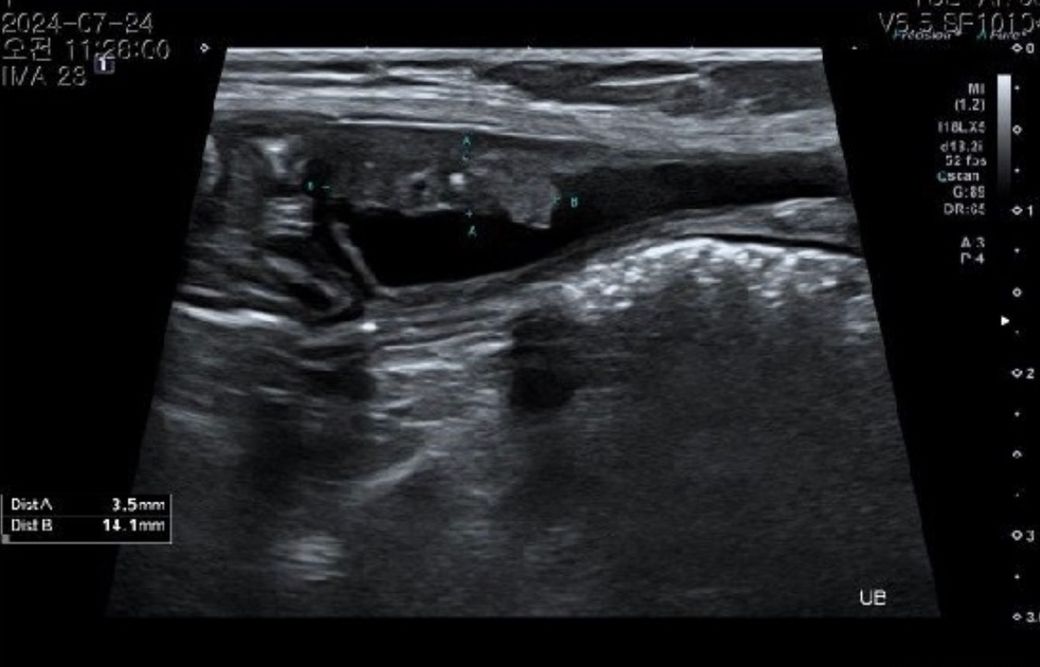

비장은 절제 수술 하기로 했습니다 .초음파상 혹들 어때보이나요ㅠㅠ?신장 물혹은 커서 수술할 때 물 빼도 무리는 안될까요????

초음파상 물혹이 있어보이고 저부분은 물혹을 주사기로 찔러서 배액하기 보다는 그냥 두거나 또는 알코올을 주입해서 없애버리기도 합니다.

비장쪽에도 종양이 생긴 것 같은데 해당 부분은 CT촬영 후 전이소견 여부를 제대로 확인 후 수술하시는 것을 권유드립니다.